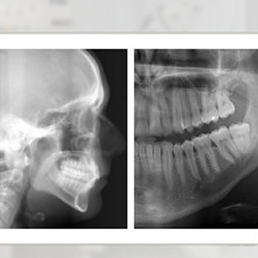

Pakiet badań pozwalający na diagnostykę obszaru szczęki, żuchwy, stawów skroniowo- żuchwowych oraz zatok szczękowych.

Badanie RTG obrazujące obszar szczęki, żuchwy, stawów skroniowo- żuchwowych oraz zatok szczękowych.

Badanie RTG czaszki pozwala ocenić zgryz Pacjenta oraz pobrać wymiary niezbędne przy wyborze aparatu ortodontycznego.

- RTG cefalometryczne (cefalometria) – wykorzystywane w ortodoncji. Pokazuje profil czaszki i ustawienie zębów względem struktur kostnych twarzoczaszki. To jedno z podstawowych badań przy planowaniu leczenia wad zgryzu.